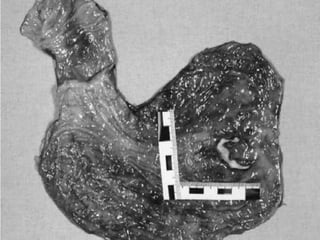

A well known complication traumaTrauma and Disease:Trauma and Alimentary system:Whenever a history is obtained of blow to the abdomen, the patient should be kept under observation until all likelihood of a ruptured abdominal viscous can be dismissed.

A well knowncomplication traumaTrauma and Disease:Trauma and Alimentary system:Whenever a history is obtained of blow to the abdomen, the patient should be kept under observation until all likelihood of a ruptured abdominal viscous can be dismissed.